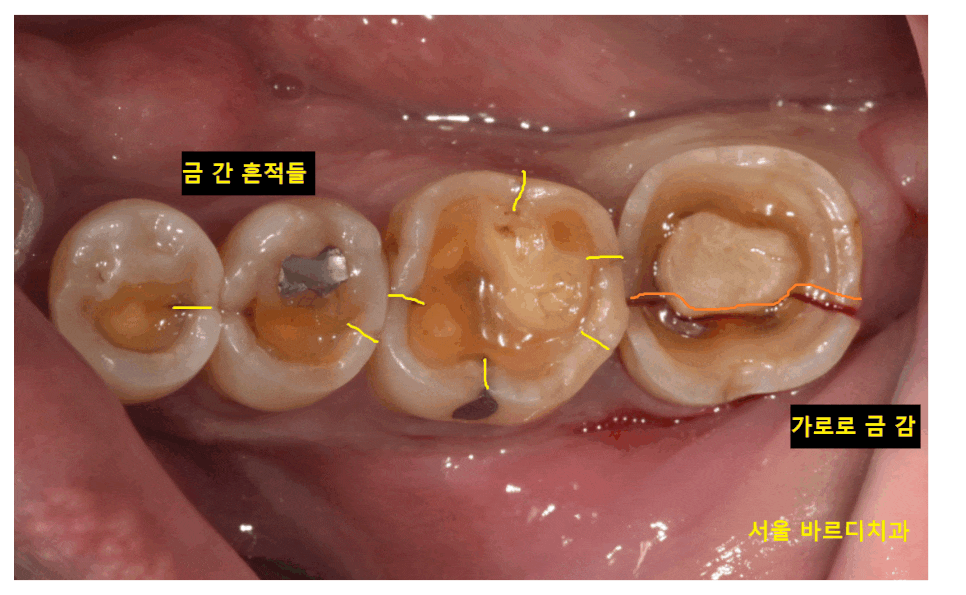

23.10.16

육안으로 보기에도 금이 보이죠~

미세한 실금은 저도 있습니다.

조심히 사용하고 증상이 없으면

딱히 치료를 안해도 되지만

환자분처럼 치아가 분리될 정도로

금이가면 뽑고 임플란트를 해주어야해요.